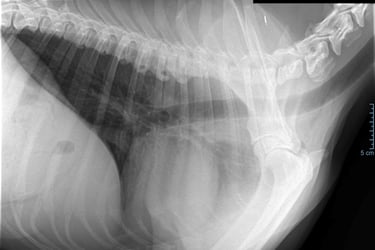

Hartonderzoek - Echocardiografie - Electrocardiografie (EKG) - Radiografie

Radiografie (RX)

Een RX is geschikt om botbreuken, een longontsteking, de hartgrootte, arthrose,....op te sporen.

Als de hond - kat niet lang genoeg stil kan blijven liggen dan is een verdoving noodzakelijk. Voor RX van het heupgewricht is een volledige verdoving noodzakelijk.